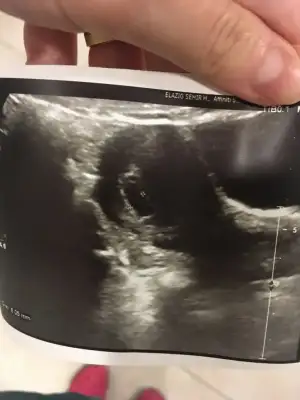

Aynen canım hemde nası bos gebelik gecirdim Ondan cok korkuyorum ama bakalım cuma belli olur bişeyler Seninkide minnoş daha😊 Benimkise bu teyzesi

Ay cok sevindim ya iyiki alttan baktırmıssın 😊 benim kese net gözüktü üstten büyüktü demekki alttan baksa benimde varsa herşey cıkıcaktı Bana pazartesi 5 haftalık dedi seninle yakın sanırım